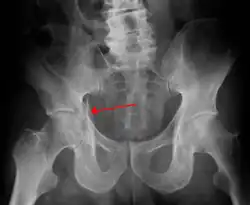

Fractures of the acetabulum occur when the head of the femur is driven into the pelvis. This injury is caused by a blow to either the side or front of the knee and often occurs as a dashboard injury accompanied by a fracture of the femur.[1]

High anterior column fracture 3 D CT scan picture -

High anterior column fracture after fixation with screws and plates